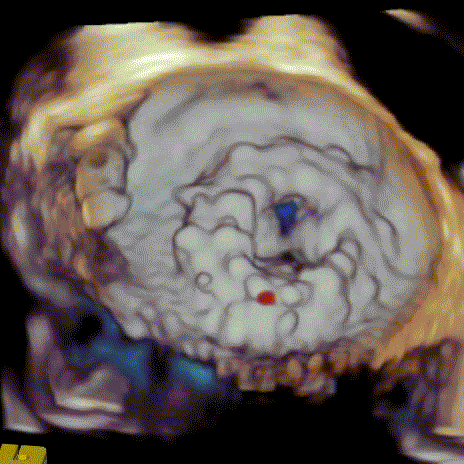

病例1(二尖瓣“瓣中瓣中瓣”):

患者男性,60岁, 2016年行二尖瓣置换术+心脏搭桥术,植入29号生物瓣一枚。后瓣膜损毁2019年经心尖途径行二尖瓣“瓣中瓣”手术,植入27# 自膨式介入瓣一枚。患者一周前无明显诱因发生活动后气喘,伴胸闷,复查心脏超声提示自膨式介入瓣损毁,瓣膜轻度狭窄伴重度关闭不全。患者合并肾衰,长期透析,既往行右侧股骨头置换,右小腿截肢。STS评分8.589%,患者病情复杂,属于常规外科再次换瓣手术高风险患者。

经过手术团队充分讨论病例资料,模拟在首次手术生物瓣环与第二次手术瓣膜内植入定位更精准的佰仁Renato®球扩式瓣中瓣,以有效治疗二尖瓣自膨式介入瓣毁损。手术按照术前讨论方案进行,过程顺利,成功植入27号Renato®球扩瓣,瓣膜植入位置理想,启闭功能表现出色。左室造影及经食道超声观察无明显瓣中及瓣周反流,平均跨瓣压差降至8.0mmHg。

球扩瓣释放

瓣中瓣植入前

二尖瓣重度反流

瓣中瓣植入后

无明显瓣中及瓣周反流